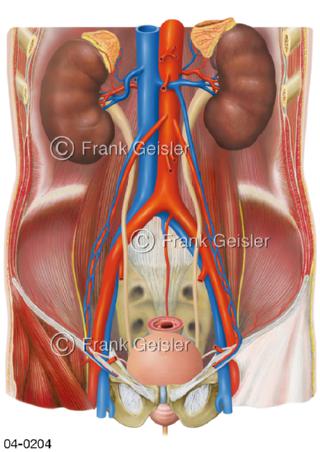

Bildergalerie Topografie Organe

Bilder zur topografischen Anatomie, die Lage der Organe und die Strukturen nach ihren räumlichen Lagebeziehungen zueinander, Übersicht der inneren Organe im Kopf und im Rumpf, Topografie der Organe im Brustraum (Thorax) und im Bauchraum (Abdomen)